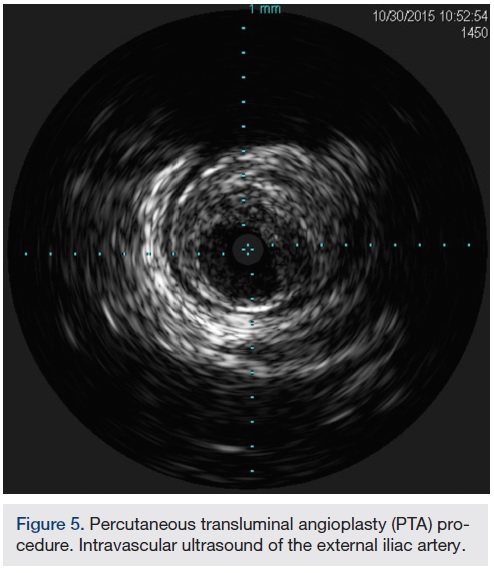

In view of the increased complexity of this situation and potentially prolonged procedure times with increased risk of complications, we chose to stage the procedure in two phases: peripheral and coronary. Accordingly, the patient was brought in, the left common femoral artery was accessed using a micropuncture technique, and a 10 cm, 7 French sheath was placed in the artery. Angiography of the left iliofemoral system was performed using a 4 French multipurpose catheter. This was followed by IVUS, revealing a 38.1 mm2 reference segment area and a minimum 8.6 mm2 stenosis area, equating to an 80% area stenosis within the left external iliac artery (Figures 5-6). The wire was exchanged for a 260 cm Rosen wire (Cook Medical) and the lesion was first predilated with a Workhorse II 6 mm balloon (AngioDynamics) at 10 atmospheres for 60 seconds for two successive inflations. The balloon was then removed over the wire and the short 7 French sheath was exchanged over the wire for a 25 cm, 7 French sheath, which was advanced over the Rosen wire into the distal aorta. An 8 mm x 38 mm x 120 mm iCast covered stent (Atrium Medical) was then advanced to the level of the stenosis and unsheathed via retraction of the 7 French long sheath. The stent was deployed at 10 atmospheres for 60 seconds. There was still a small waist in the proximal stent and this was post dilated with the stent balloon at 13 atmospheres for 90 seconds with excellent angiographic result and no evident perforation or dissection, yielding 0% residual stenosis (Figure 7).